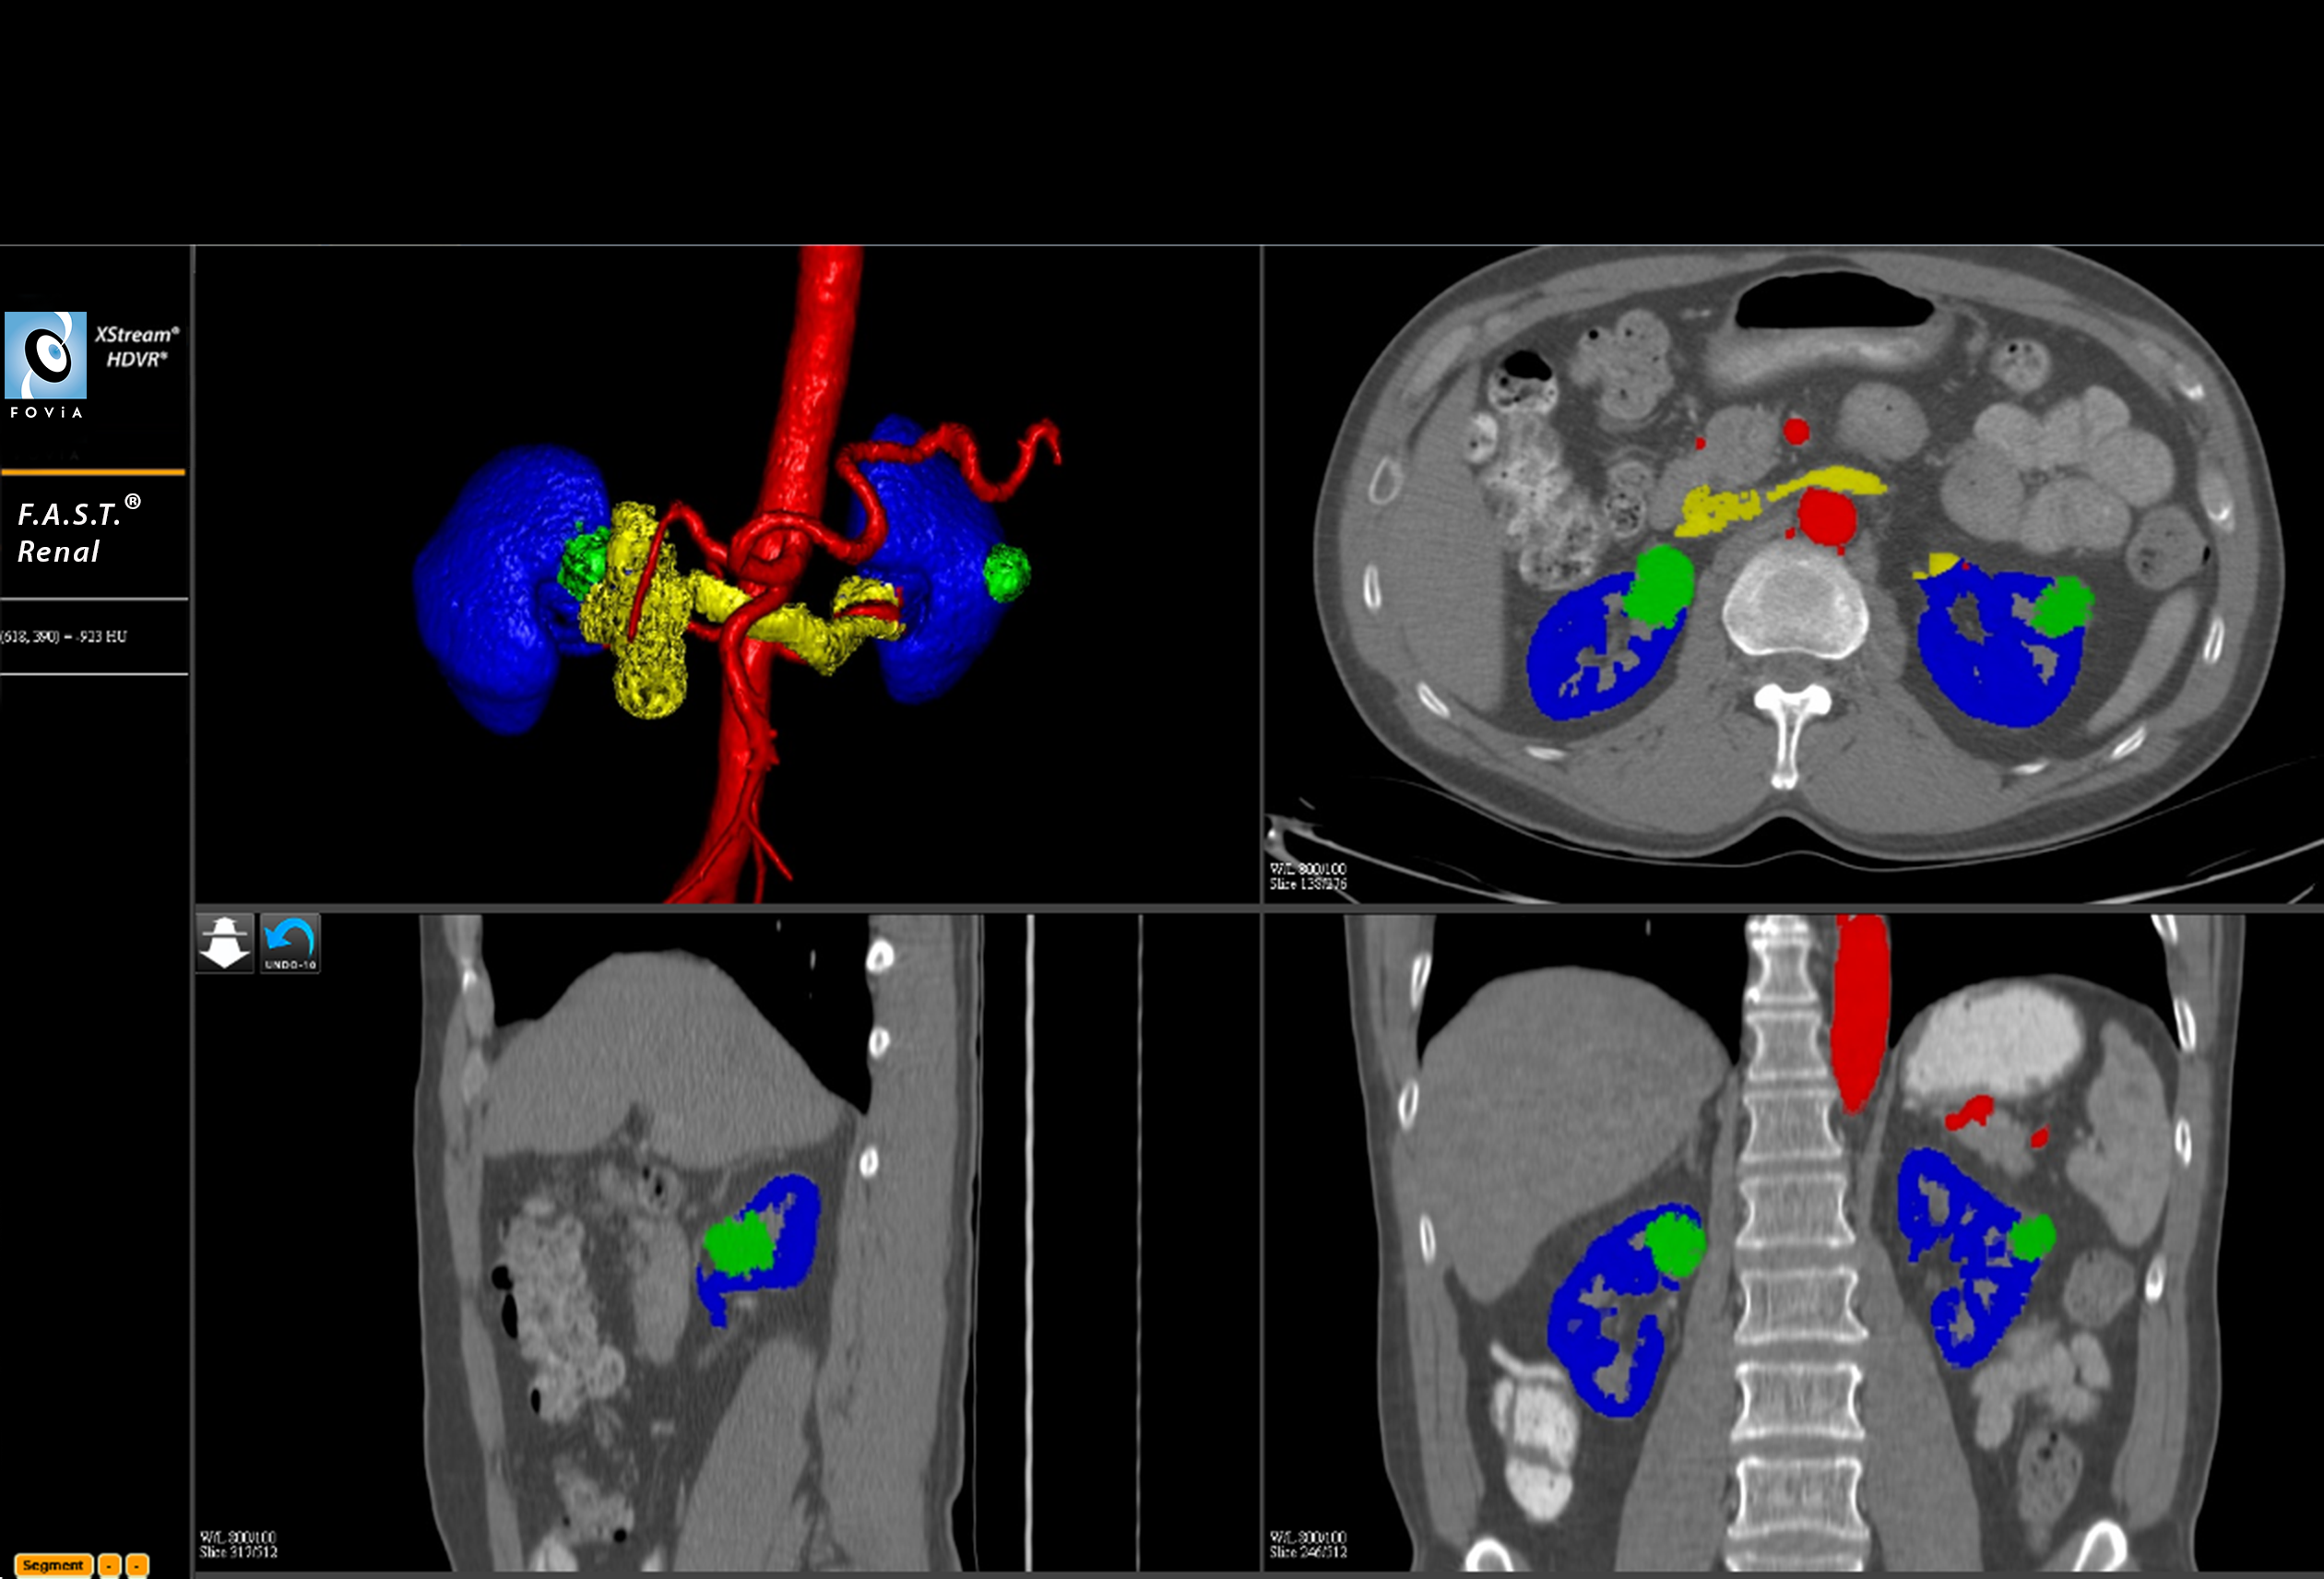

F.A.S.T. Renal Workflow

F.A.S.T. Renal Workflow